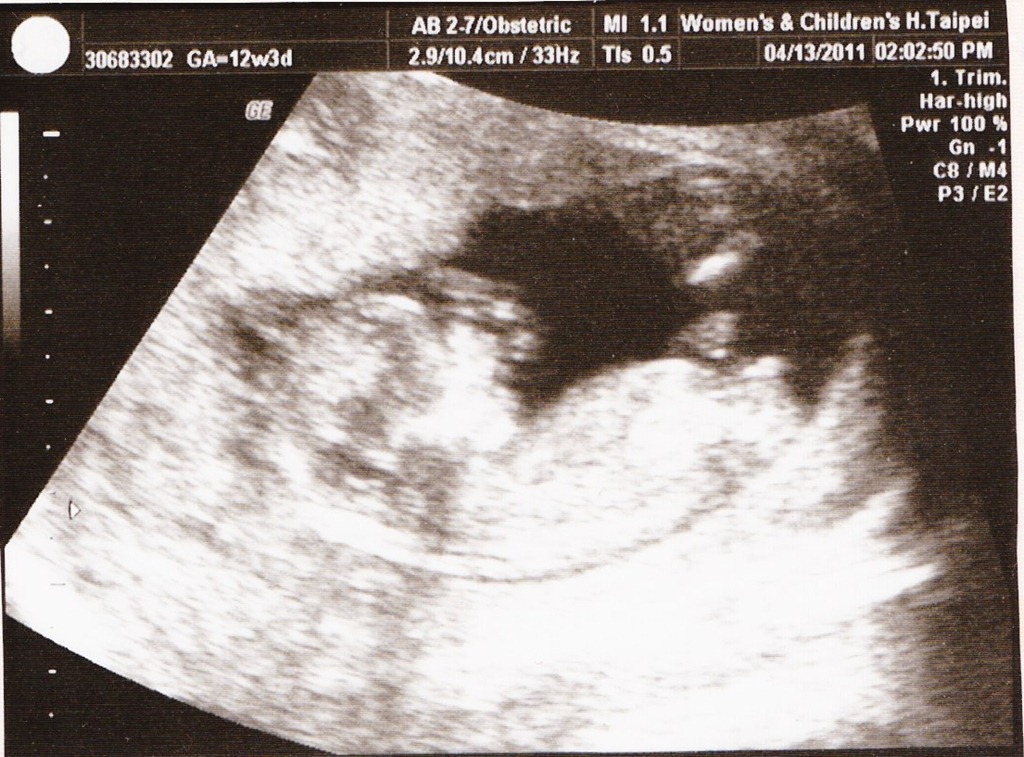

100/4/23:14周大,頸部透明帶的檢查結果是1.6公分,換算唐氏症機率是15960分之一,是很安全的指數。這次拍出我的照片,頭型輪廓又更加明顯、身體及手腳都看的到。